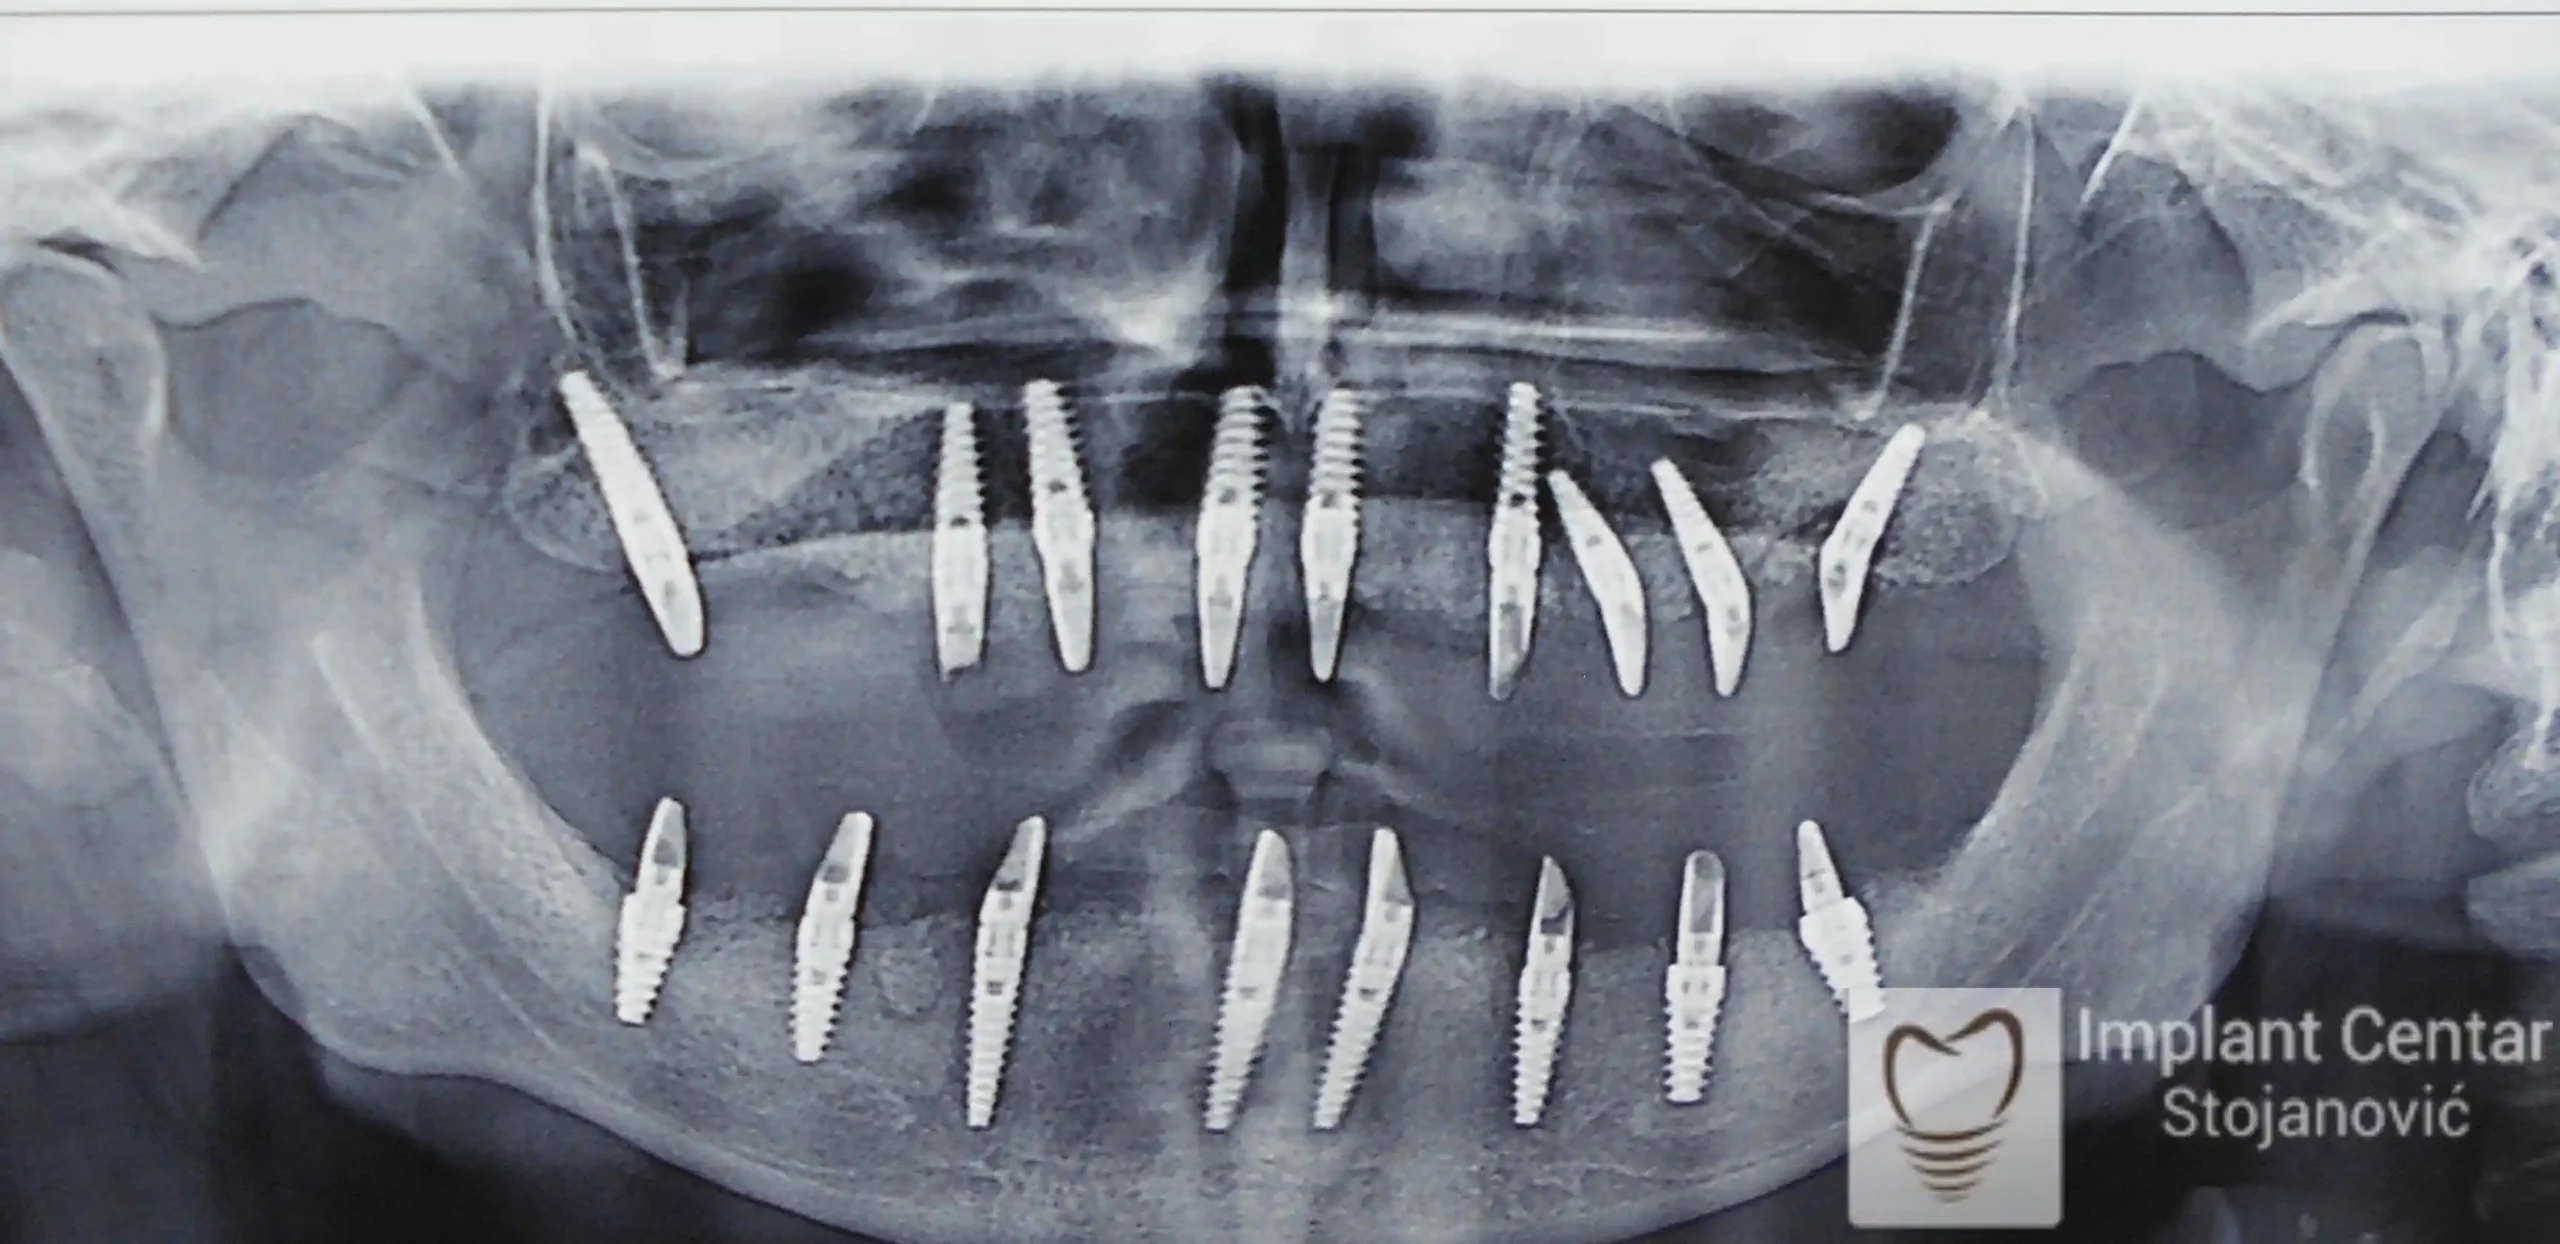

Zbog toga je plan terapije uključivao vađenje svih preostalih zuba i ugradnju implantata u gornjoj i donjoj vilici. U gornjoj vilici postavljena su i dva tuberopterigoidna implantata, kao zamena za sinus lift proceduru, što se može videti na ortopan snimku nurađenom odmah nakon ugradnje (slika 3).